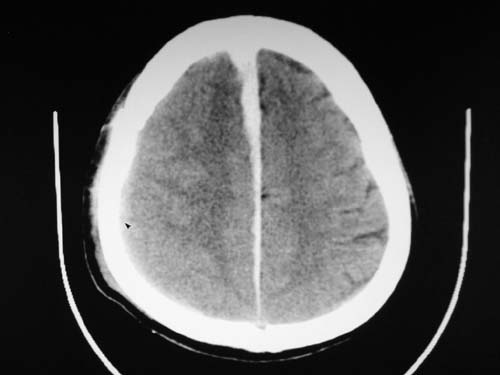

标题: CT17020:是硬膜下的吗?

脑中线内血肿,是硬膜下的吗?

脑中线内血肿——硬膜下血肿。

脑中线内血肿——硬膜下血肿。我们一般认为中线即可是硬膜下,也可是蛛网膜下腔的。边缘锐利,张力高的考虑硬膜下的,边缘模糊的,考虑下腔的。如果有老师有肯定的答案,麻烦下给我发个短信

支持镰旁硬膜下血肿,颅骨骨折,头皮损伤.

这个病人年龄不小吧,右侧脑沟不清,中线结构稍有左移,右侧额颞顶及右镰旁硬膜下血肿,另有蛛血,骨折。

外伤后引起的颅骨骨折、硬膜下血肿、皮下血肿,颅骨骨折引起的矢状窦破裂,形成大脑纵裂内血肿。